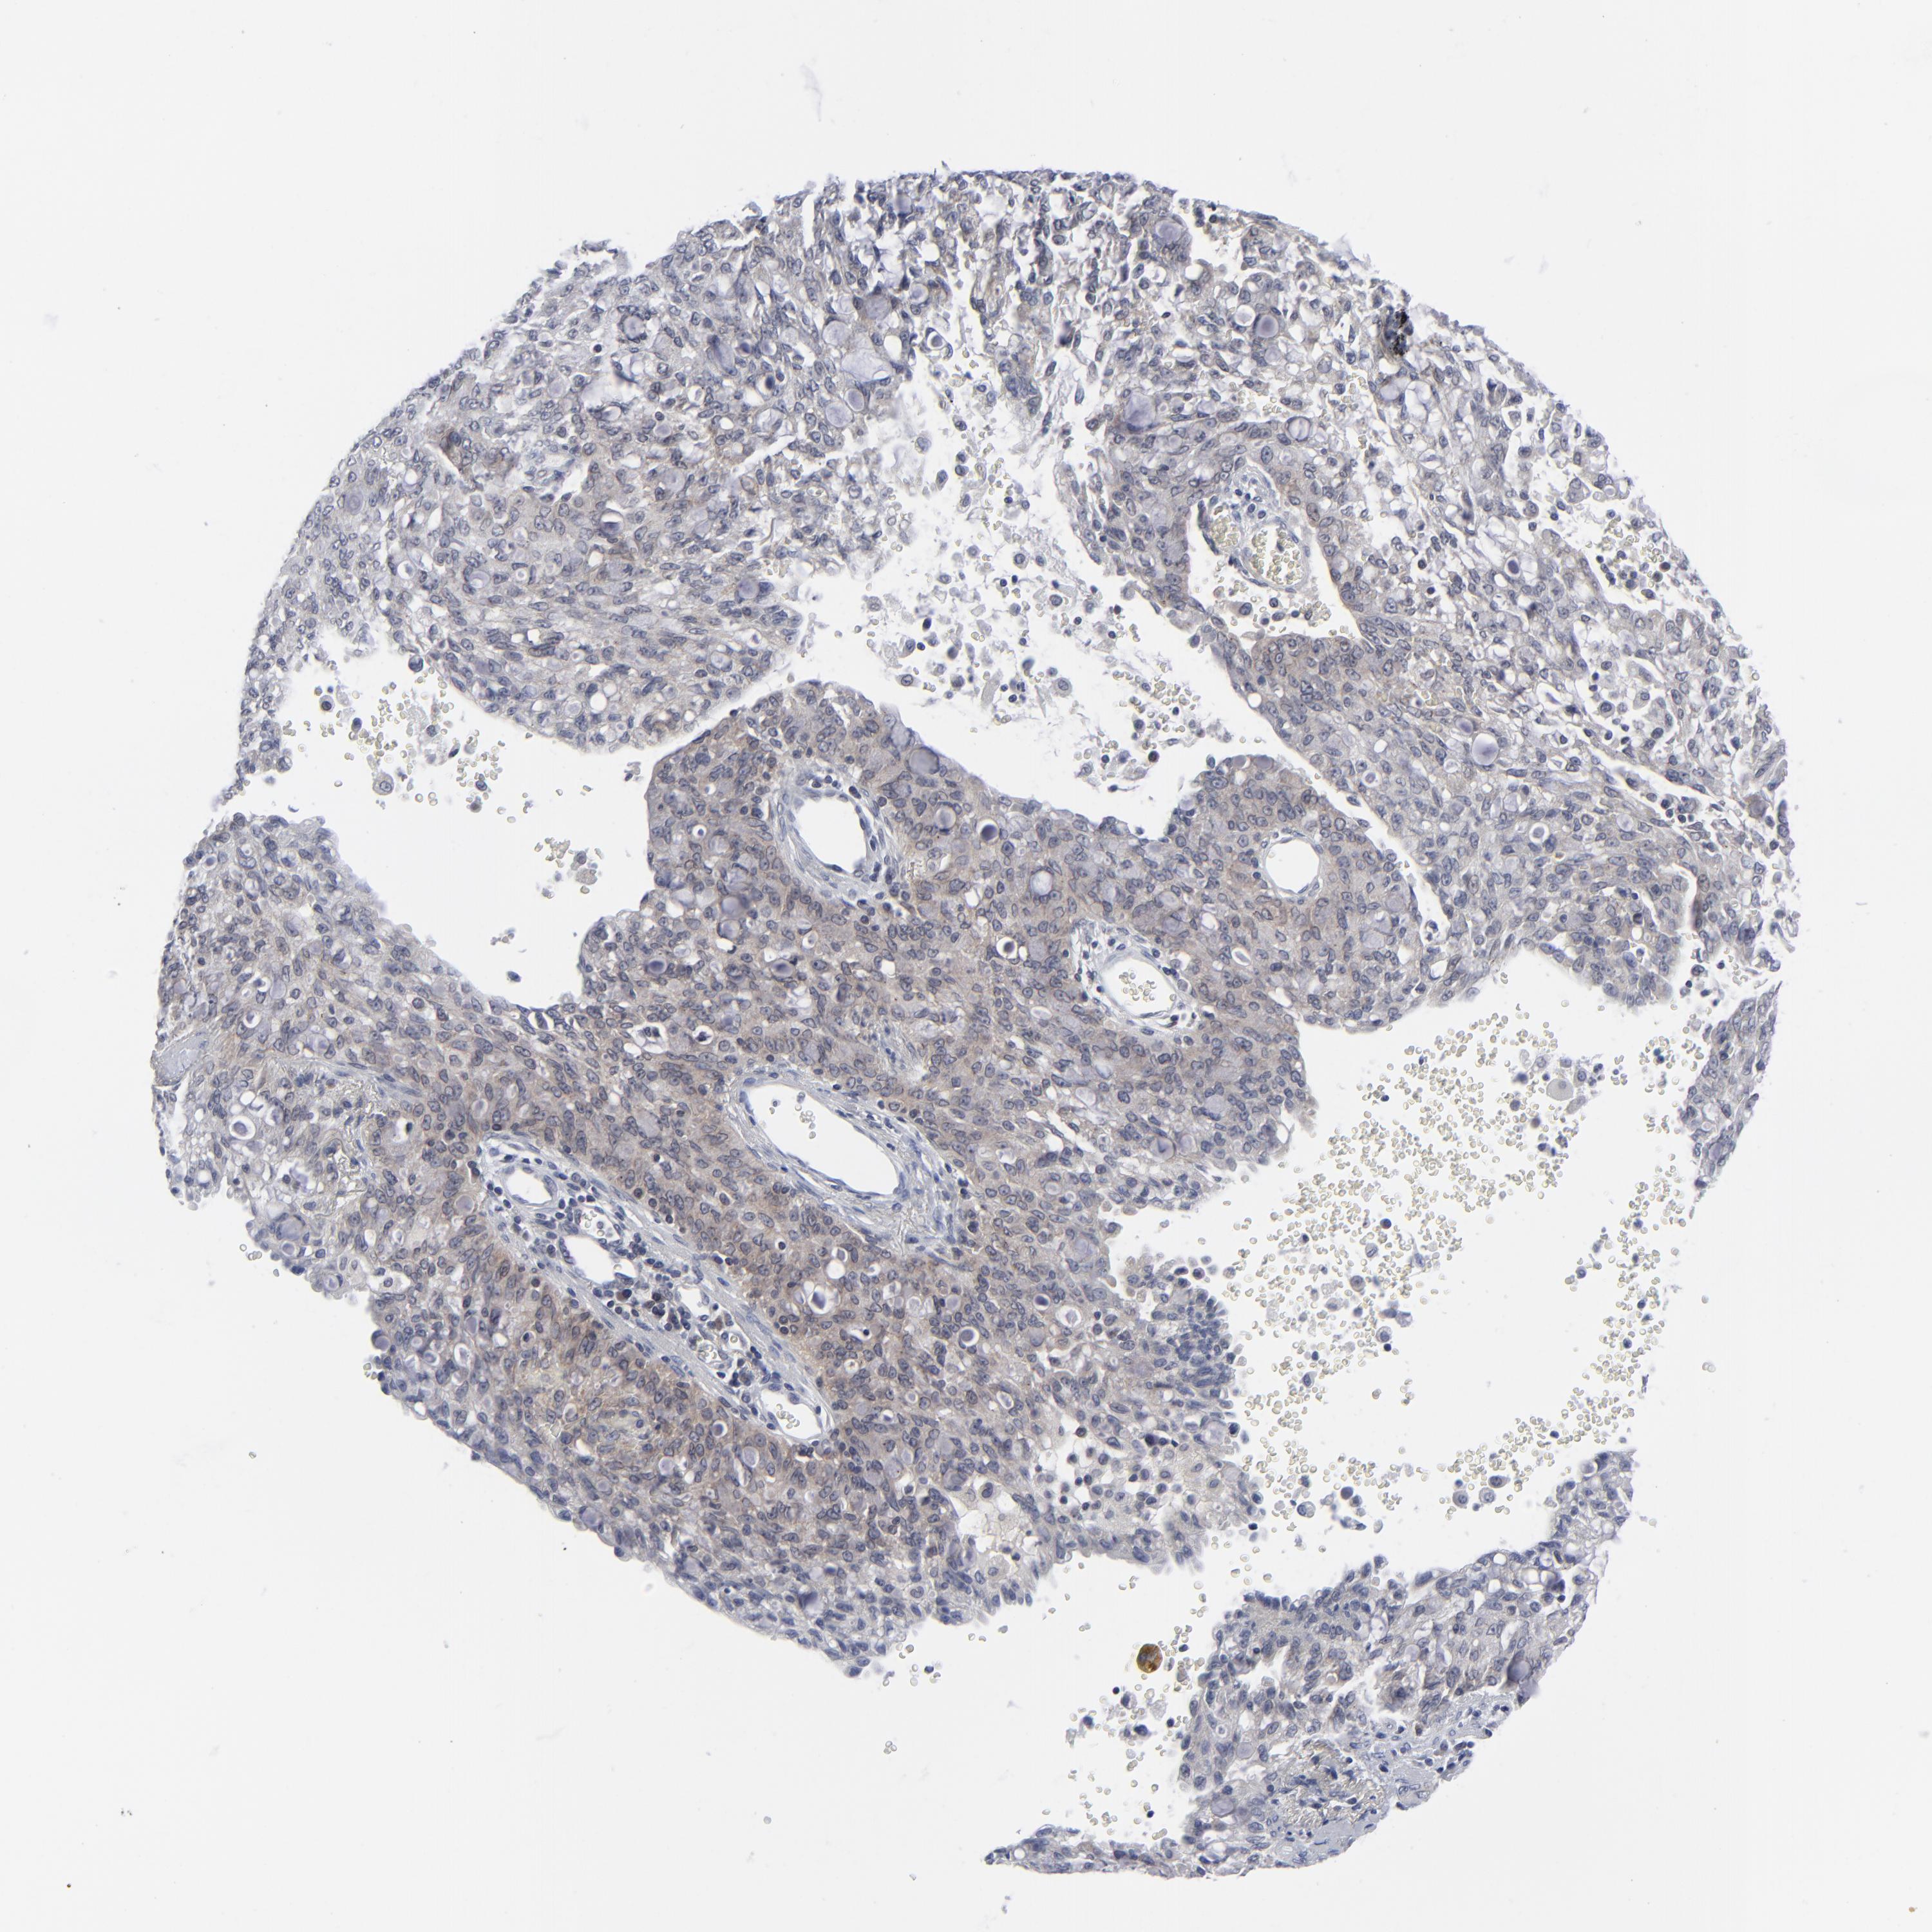

CANCER LUNG CANCER Show tissue menu